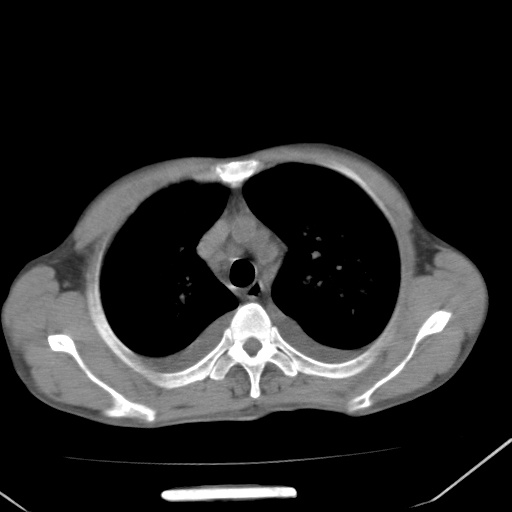

男、42岁、咯血3天。既往有甲亢、贫血、血尿蛋白尿史多年。血象:wbc:6.   中性粒:70.6%。

双肺野对称性磨玻璃影,分布于内中带,双侧胸水,患者有咯血。

双肺野广泛对称性磨玻璃影、实变影,以肺门为中心,主要分布于内中带,符合典型肺泡性肺水肿;伴双侧胸腔少量游离积液。结合患者既往病史且咯血就诊,支持多因素(尿毒症等)所致之肺水肿、肺出血、胸水;影像表现暂不考虑心源性水肿,且症状也不太符。需密切随诊结合临床治疗等进一步明确。